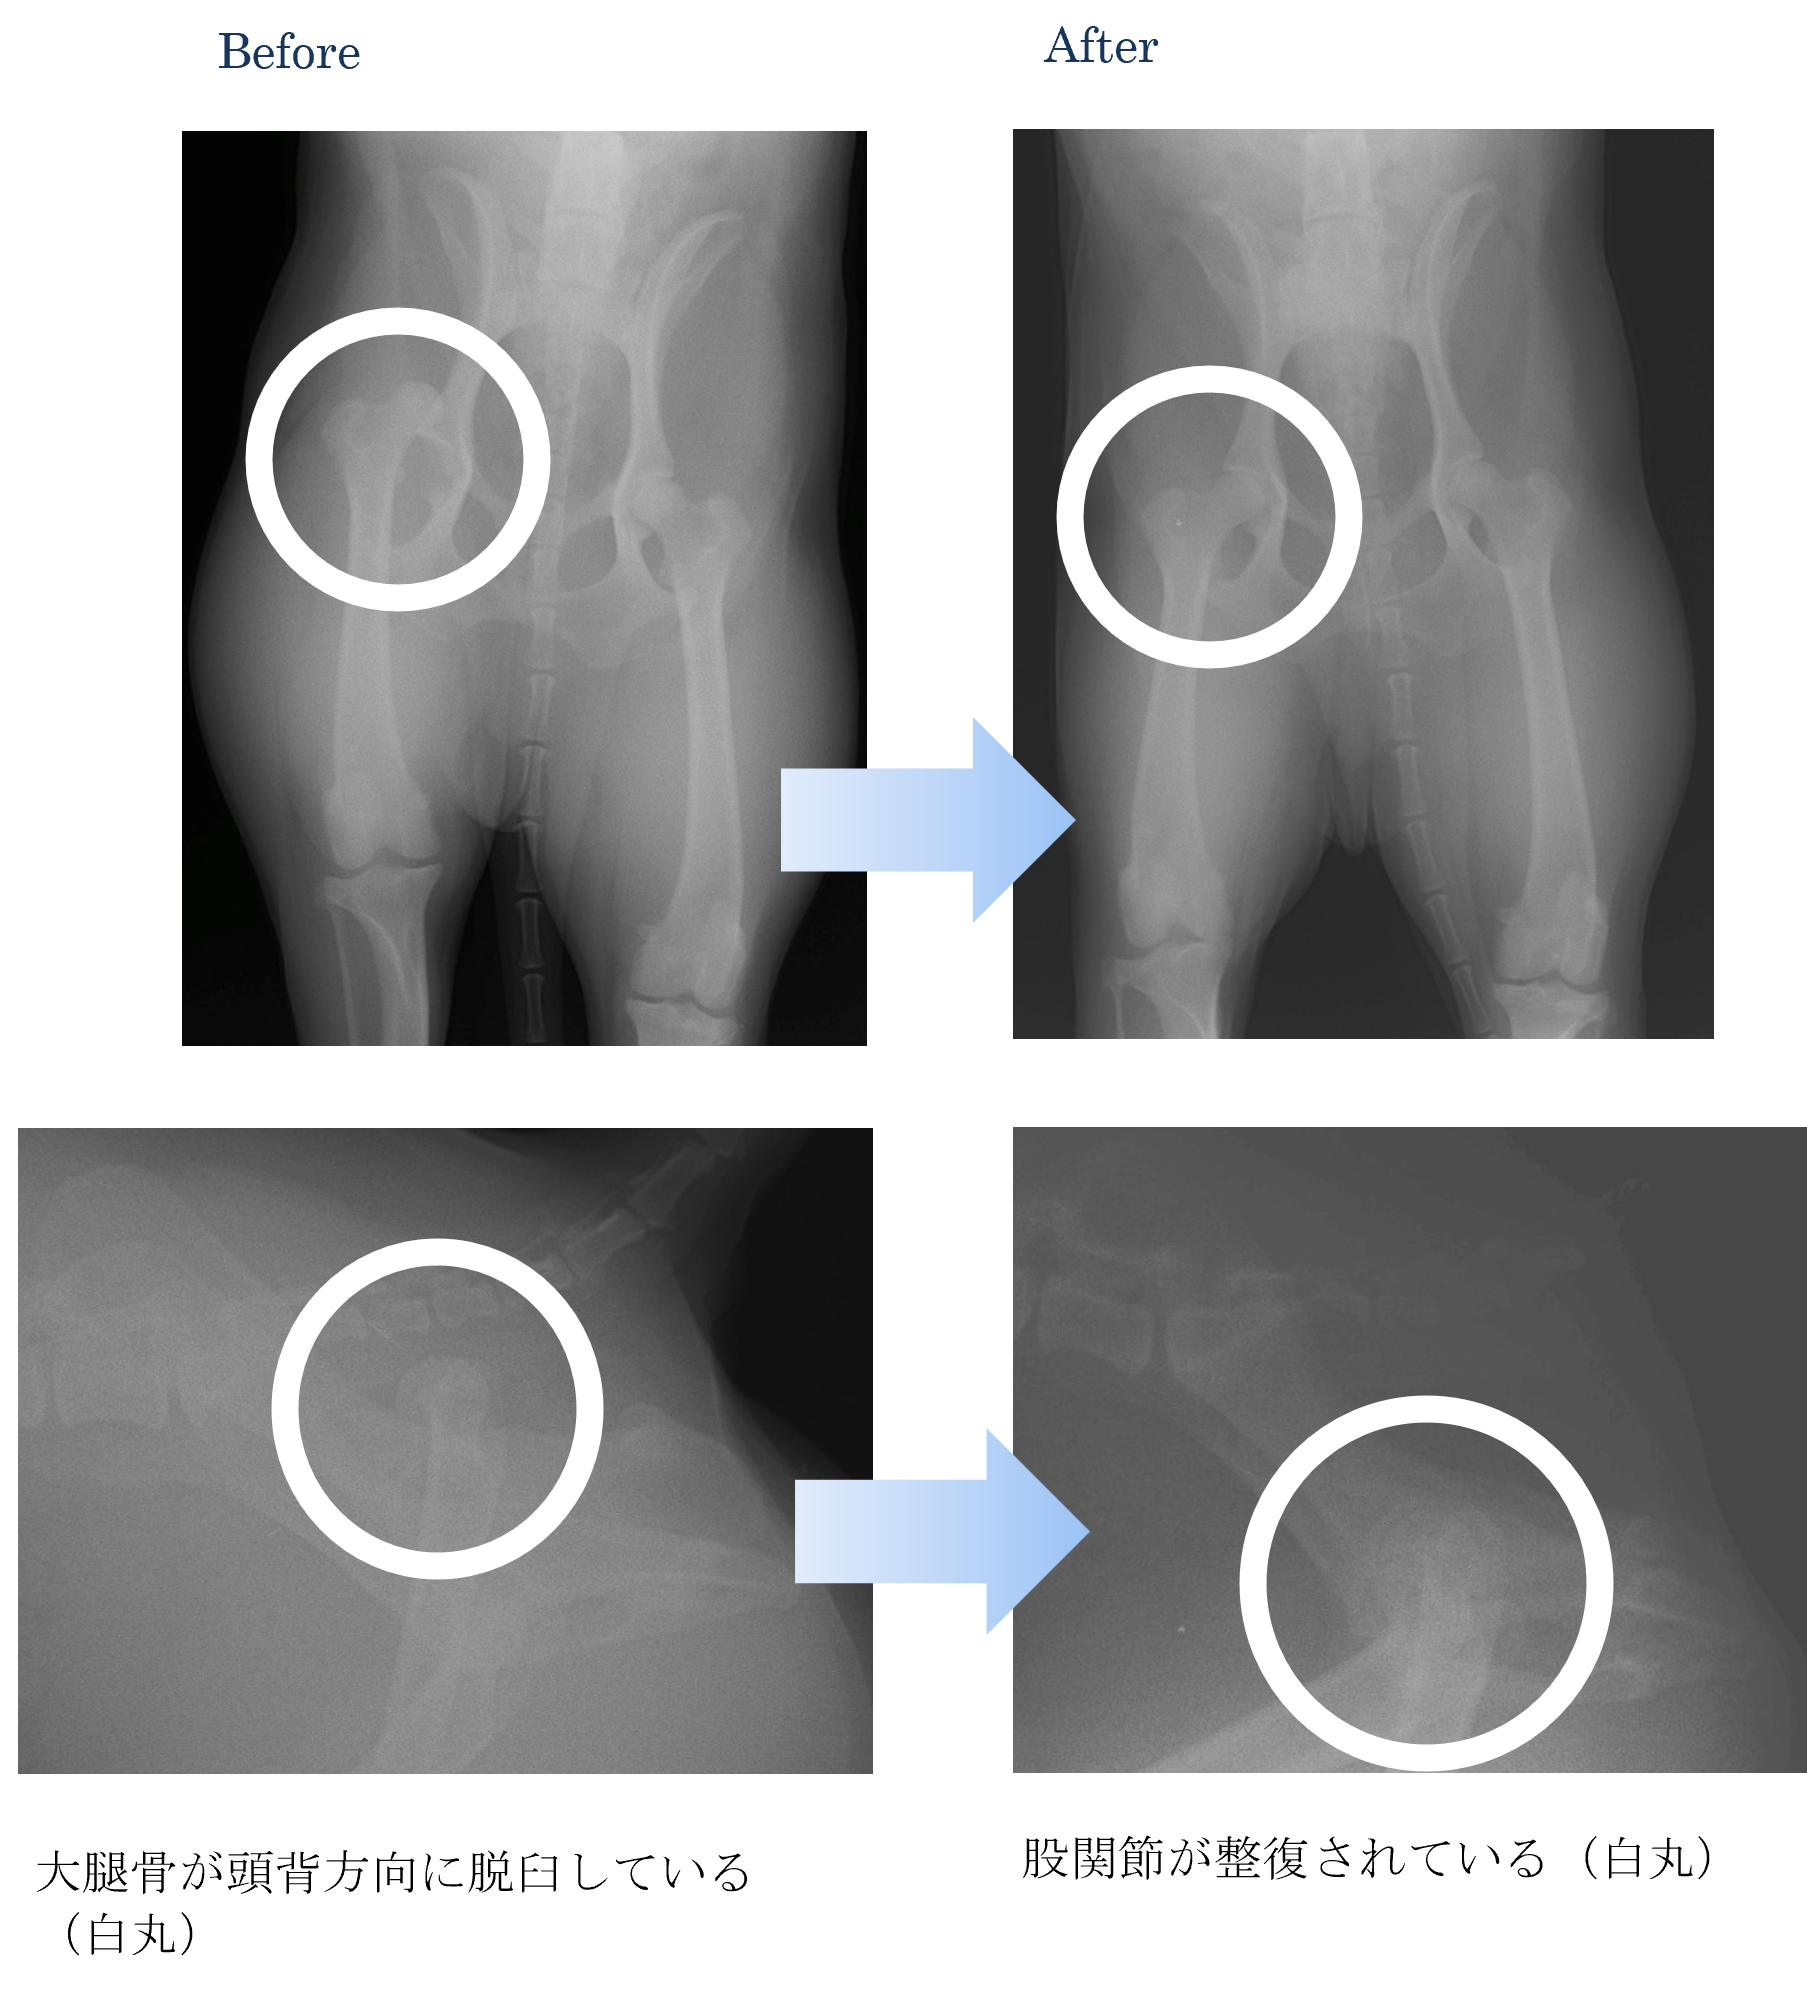

各種検査より、股関節脱臼(頭背側)と診断しました。

ご家族と相談から、膝蓋骨脱臼を整復して外固定(包帯)を実施することになりました。

股関節が安定したころに外固定を外しました。